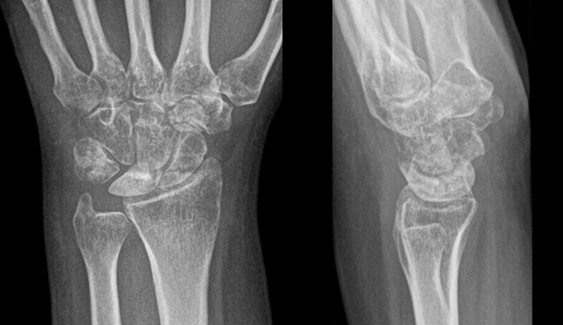

Here, we present two cases of Kienböck’s disease classified as Lichtman stage IIIc, characterized by complete osteonecrosis and a coronal fracture of the lunate, without associated cartilage damage. Both patients underwent a medial closing wedge osteotomy of the radius combined with compression screw fixation of the lunate fracture. The two patients were female, aged 42 and 47 years, with a history of wrist pain. Pre-operative imaging included standard wrist radiography, which revealed a negative ulnar variance (radiographic ulnar index), computed tomography (CT) confirming the presence of a lunate fracture, and MRI demonstrating osteonecrosis (showing a hypointense signal on T1-weighted sequences and a hyperintense signal on T2-weighted sequences, with no gadolinium enhancement). No signs of carpal instability or cartilage degeneration were observed in the surrounding structures.

- Patient A: A 42-year-old right-handed housewife presented with significant pain and stiffness in her dominant wrist persisting for 4 months. She had no history of trauma and was a non-smoker. Her medical history was notable for diabetes and a prior episode of deep vein thrombosis in the lower limb several years earlier (Fig. 1, 2, 3).

Figure 1: X-ray radiographic ulnar index of −3 mm.

Figure 2: Computed tomography scan.

Figure 3: Magnetic resonance imaging.